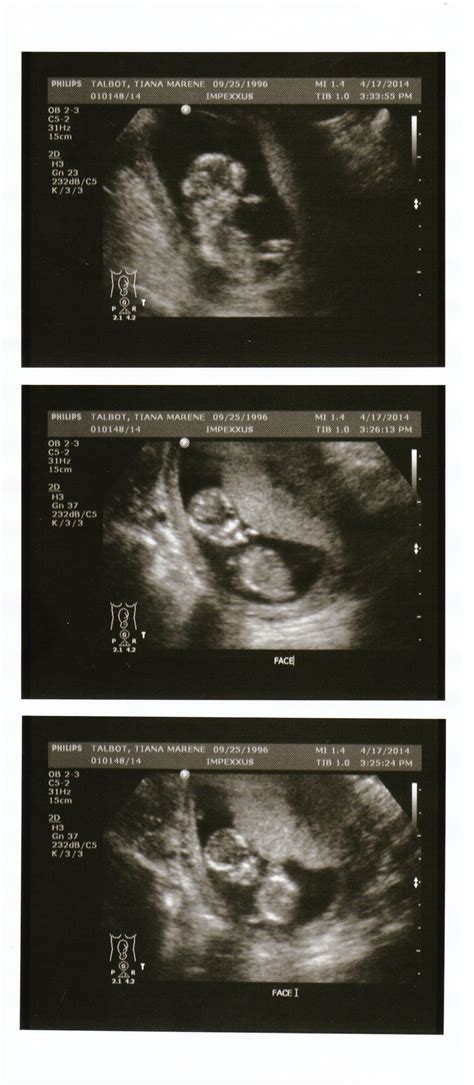

Pregnancy is an exciting journey filled with milestones, and one of the most anticipated moments is the 15 week ultrasound. This scan is a crucial part of prenatal care, providing valuable insights into the baby's development and the mother's health. Understanding what to expect during a 15 week ultrasound can help alleviate anxiety and prepare you for this important appointment.

A 15 week ultrasound is a routine prenatal check-up that uses high-frequency sound waves to create images of the developing fetus. This scan is typically performed between 14 and 16 weeks of pregnancy, but the term 15 week ultrasound is commonly used to refer to this period. The primary goal of this ultrasound is to assess the baby’s growth and development, as well as to screen for any potential abnormalities.

At 15 weeks, the baby is about the size of an apple, measuring approximately 4 inches (10.1 centimeters) in length and weighing around 2.5 ounces (70 grams). The 15 week ultrasound can reveal several key features:

• Fetal Movement: The baby becomes more active, and you may see the fetus moving, kicking, and even sucking its thumb.

• Facial Features: The baby’s facial features are becoming more defined, including the eyes, nose, and mouth. The ears are also more prominent.

• Organ Development: The baby’s organs are developing rapidly. The heart beats strongly, and the lungs, kidneys, and digestive system are forming.

• Gender Determination: In some cases, the baby’s gender may be determined during a 15 week ultrasound, although it is more accurately assessed later in the pregnancy.